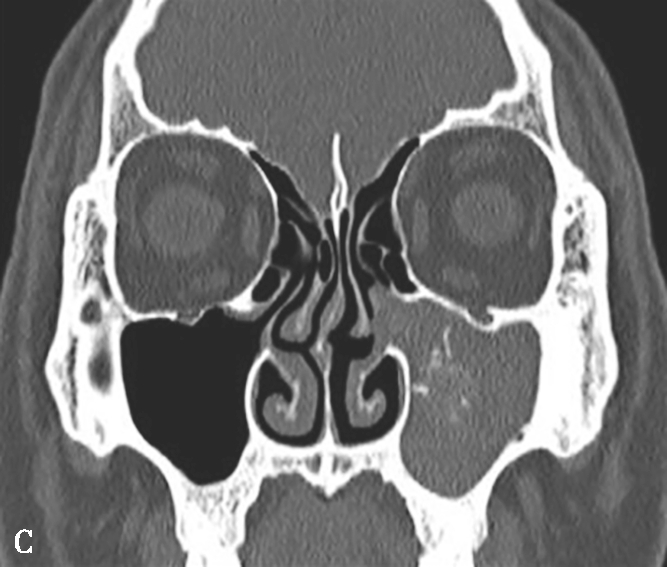

图1-3-20 慢性鼻窦炎

A~C.横断面、冠状面及矢状面CT平扫,示右侧额窦、上颌窦黏膜增厚,窦腔内可见软组织密度影,窦口鼻道复合体狭窄,右侧上颌窦窦壁骨质增生硬化、肥厚;D~F.同一患者横断面MR T 2 WI、T 1 WI及横断面增强T 1 WI,示右侧上颌窦黏膜增厚,呈T 1 WI等信号、T 2 WI高信号影,增强扫描示右侧上颌窦黏膜线样强化

4.CT表现

①平扫表现:鼻窦黏膜增厚,轻度2~5mm,中度5~10mm,重度> 10mm。黏膜下囊肿可见。严重者窦腔实变。窦壁骨质硬化、肥厚(图1-3-20A~C)。②增强扫描表现:边缘黏膜明显强化。

5.MRI表现

①T 1 WI表现:低信号多见,亦可为等或高信号。②T 2 WI表现:高信号多见,亦可为等或低信号,依分泌物内自由水与蛋白质含量而定。信号可不均匀。③增强扫描表现:边缘黏膜明显强化(图1-3-20D~F)。